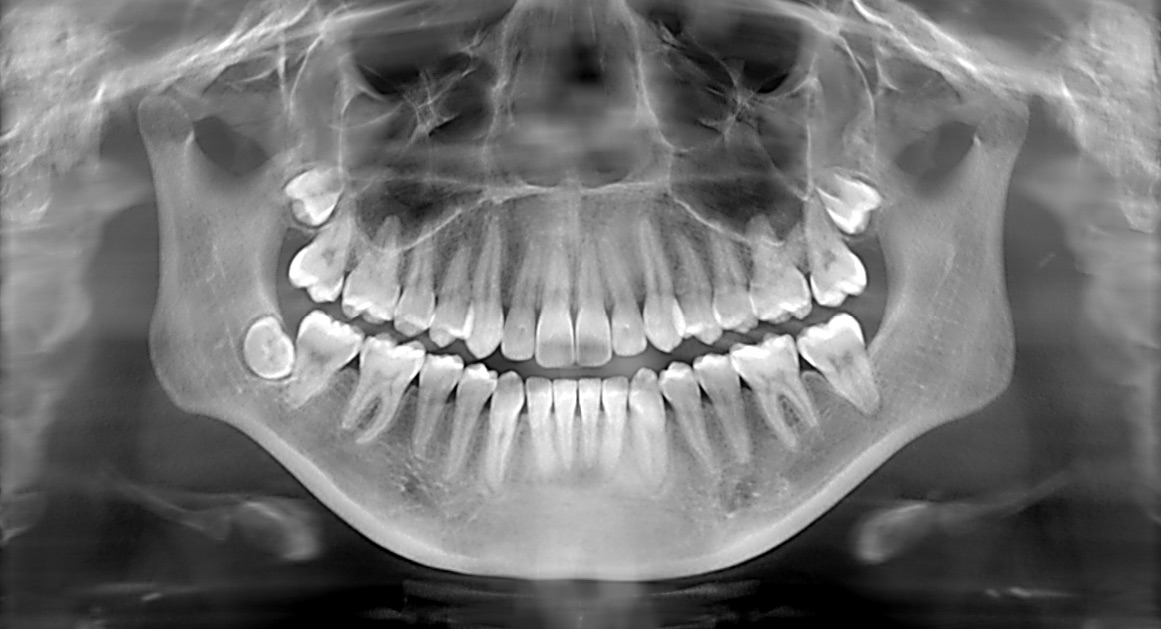

digital x-rays